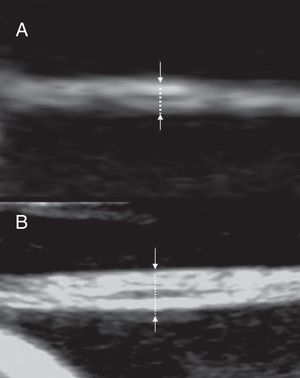

The membrane thickness can be measured with high resolution ultrasound equipments. The membrane should be imaged perpendicularly to the ultrasonic beam after magnification (Fig. 9). The most reliable site for measurement with the most reproducibility is close to the placenta (<3cm).23 The cut-off value firstly suggested to differentiate dichorionic from monochorionic twins is 2mm. Using that value Winn et al.24 report a diagnostic accuracy of 82% for monochorionicity and 95% for dichorionicity. Bracero and Bryne25 report a sensitivity of 75.7%, a specificity of 85.7%, a positive predictive value of 96.6%, and a negative predictive value of 40.0%, for determining dichorionicity. A lower cut-off of 1,5mm has been suggested for measurements made in the first trimester.14The sensitivity of membrane thickness for determining chorionicity declines with increasing gestation with a sensitivity of only 52% for dichorionicity in the third trimester.26

Evaluation of the inter-twin membrane in the second trimester. The membrane is imaged perpendicularly to the ultrasonic beam and magnified. (A) monochorionic twins: two layers may be seen and the thickness is below 2mm (B) dichorionic twins: more than two layers may be seen and the thickness is above 2mm.

Number of the layers of the inter-twin membrane The inter-twin membrane is made by four layers (amnios-chorion-chorion-amnios) in dichorionic and only two layers (amnios-amnios) in monochorionic twins. Using high resolution equipment and magnified images with the membrane perpendicular to the ultrasound beam it is possible to recognize the layers; counting more than two layers allows to diagnose dichorionicity19–29 (Fig. 9). It is useful to visualize the membrane close to its placental insertion in order to minimize the risk of error due to the folding back of a monochorionic membrane on itself thus appearing to have four layers.